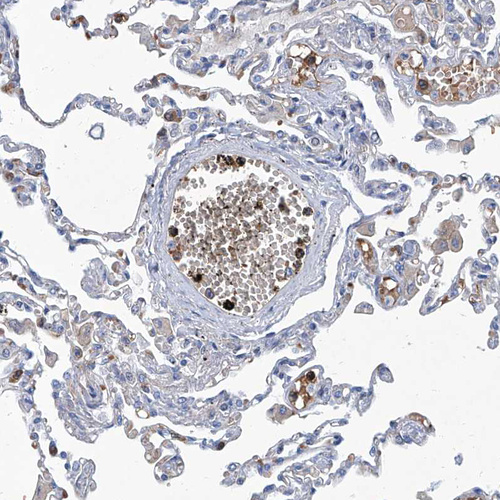

Immunohistochemical staining of human spleen shows moderate membranous positivity in cells in white pulp.